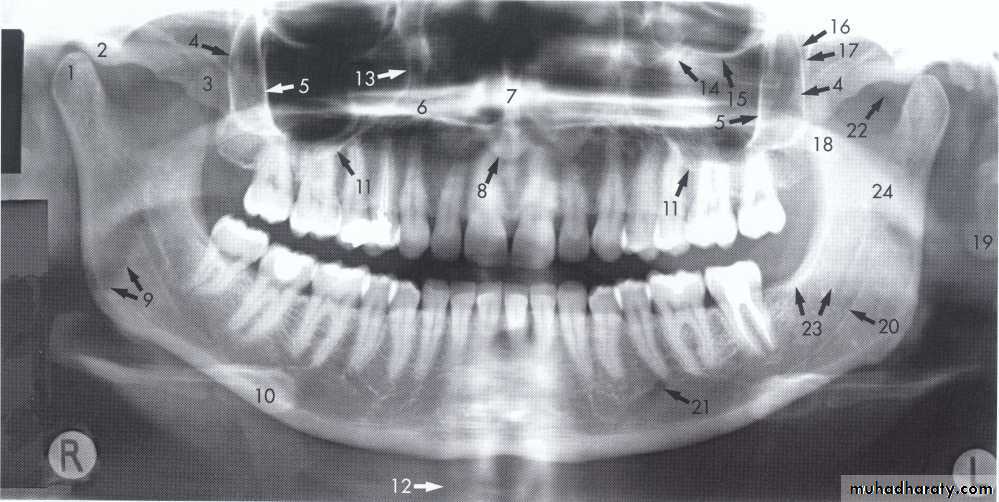

1, Mandibular condyle. 2, Articular eminence. 3, Coronoid process of mandible superimposed on zygomatic arch. 4, Posterior wall of maxillary sinus. 5, Posterior wall of zygomatic process of maxilla. 6, Hard palate. 7, Nasal septum. 8, Tip of nose. 9, Dorsum of tongue. 10, Hyoid superimposed over inferior border of mandible. 11, Inferior border of maxillary sinus. 12, Image of cervical spine. 13, Medial border of maxillary sinus. 14, Infraorbital canal. 15, Infraorbital rim. 16, Pterygomaxillary fissure. 17, Anterior border of the pterygoid plates. 18, Lateral pterygoid plate superimposed over soft palate and coronoid process of mandible. 19, Ear lobe. 20, Inferior border of mandibular canal. 21, Mental foramen. 22, Posterior wall of nasopharynx. 23, Inferior border of mandible superimposed from opposite side. 24, Soft palate over mandibular foramen of mandible.